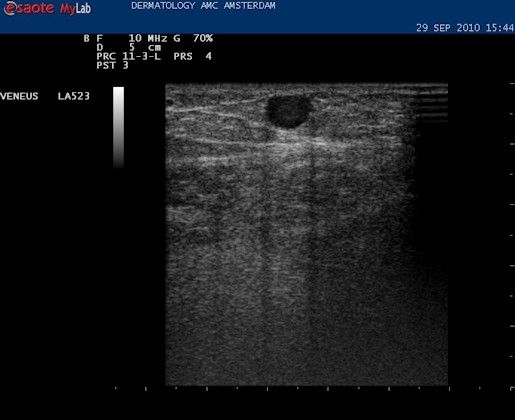

| De volgende stap is om de VSM te vervolgen naar de oorsprong in de lies, daar waar de VSM ontspringt uit de vena femoralis superficialis. Hiervoor proberen we de Mickey Mouse figuur in beeld te krijgen die hier boven te zien is. Vaak verschijnt dat al als de echokop in de liesplooi wordt gezet. Met de markering op de kop naar boven lateraal. Dan is het vat in het midden de vena femoralis. Het linker oortje, kleinere diameter, is de arterie, en het rechter oortje is de vena saphena magna. |

| Anatomie liesplooi. Lichtblauw: vena femoralis, diep systeem. Donkerblauw: vena saphena magna, oppervlakkig systeem. Rood: arteria femoralis. In de liesplooi precies waar de VSM aftakt vormen deze drie vaten de Mickey Mouse figuur. Als de echoknop markering naar lateraal staat is het rechteroortje altijd de VSM. |